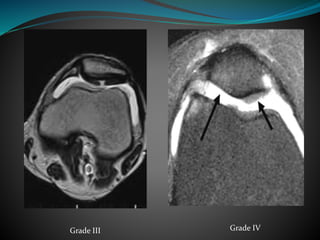

Grade MRI finding

I Focal signal intensity changes without contour deformity

(difficult to assess on MRI)

II Focal signal intensity change and contour bulge (partial

thickness)

III Focal signal intensity change, contour irregularities, cartilage

thinning and fluid extension into cartilage (full thickness)

IV Similar to stage III with defects extending to the cortical bone

(with subchondral bony changes)

Normal GradeII Grade II

Grade IVGrade III